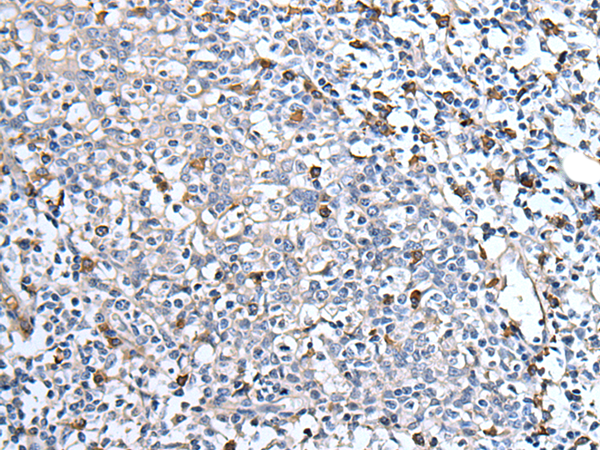

- The image is immunohistochemistry of paraffin-embedded Human tonsil tissue using P12718(MEN1 Antibody) at dilution 1/40. (Original magnification: ×200)